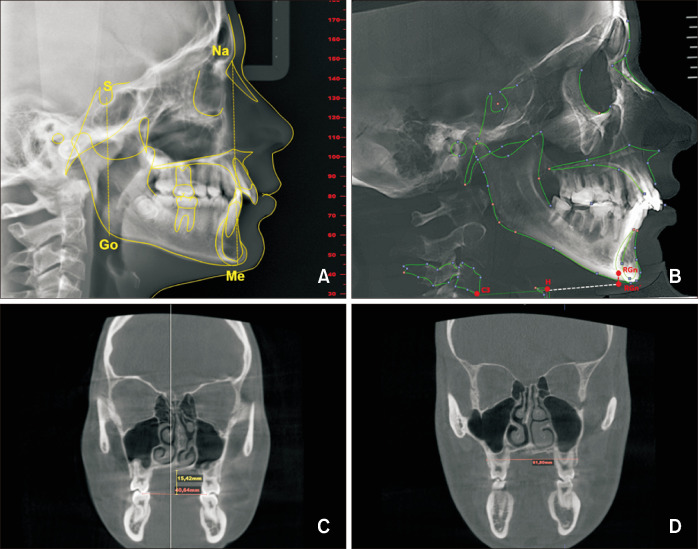

目的方法:使用 NemoFab Ortho 软件分析随机选取的 106 名正畸患者的锥形束计算机断层扫描图像:方法:使用 NemoFab Ortho 软件分析了随机抽取的 106 名正畸患者的锥形束计算机断层扫描图像。评估的牙齿骨骼变量包括面部前高(AFH)、面部后高(PFH)、PFH/AFH 比值、舌骨位置、上颌宽度(MW)和腭深。我们还使用相同的软件评估了 UA 体积(按解剖区域和整体进行评估)。我们还评估了不同年龄组和性别组之间 UA 变量的潜在差异。我们使用皮尔逊相关系数(R)计算了牙骨质参数和 UA 体积之间的相关性。方差分析和学生 t 检验用于评估不同年龄和性别间 UA 变量的差异。统计分析使用 SPSS 软件(Windows 版本 26)进行:该研究发现,PFH、AFH 和 MW 是与 UA 体积最密切相关的牙骨质参数。然而,ANB 角与 UA 体积没有明显的相关性。此外,不同年龄组的 UA 体积也存在差异。在 "8-12 "和"≥16 "年龄组中,口咽和咽部体积均存在性别差异:总之,我们的研究结果表明,UA体积与牙齿骨骼参数之间存在显著相关性,尤其是与面部高度和MW相关的参数。

Methods: Cone-beam computed tomography images of 106 randomly selected orthodontic patients were analyzed using NemoFab Ortho software. The dentoskeletal variables assessed were anterior facial height (AFH), posterior facial height (PFH), PFH/AFH ratio, hyoid position, maxillary width (MW), and palatal depth. The UA volume (evaluation in anatomical regions and as a whole) was also assessed using the same software. We also evaluated potential differences in UA variables between age and sex groups. The correlation between the dentoskeletal parameters and UA volume was calculated using the Pearson correlation coefficient (R). Analysis of variance and Student's t test were performed to assess differences between age and sex for UA variables. Statistical analyses were performed using SPSS software (version 26 for Windows).